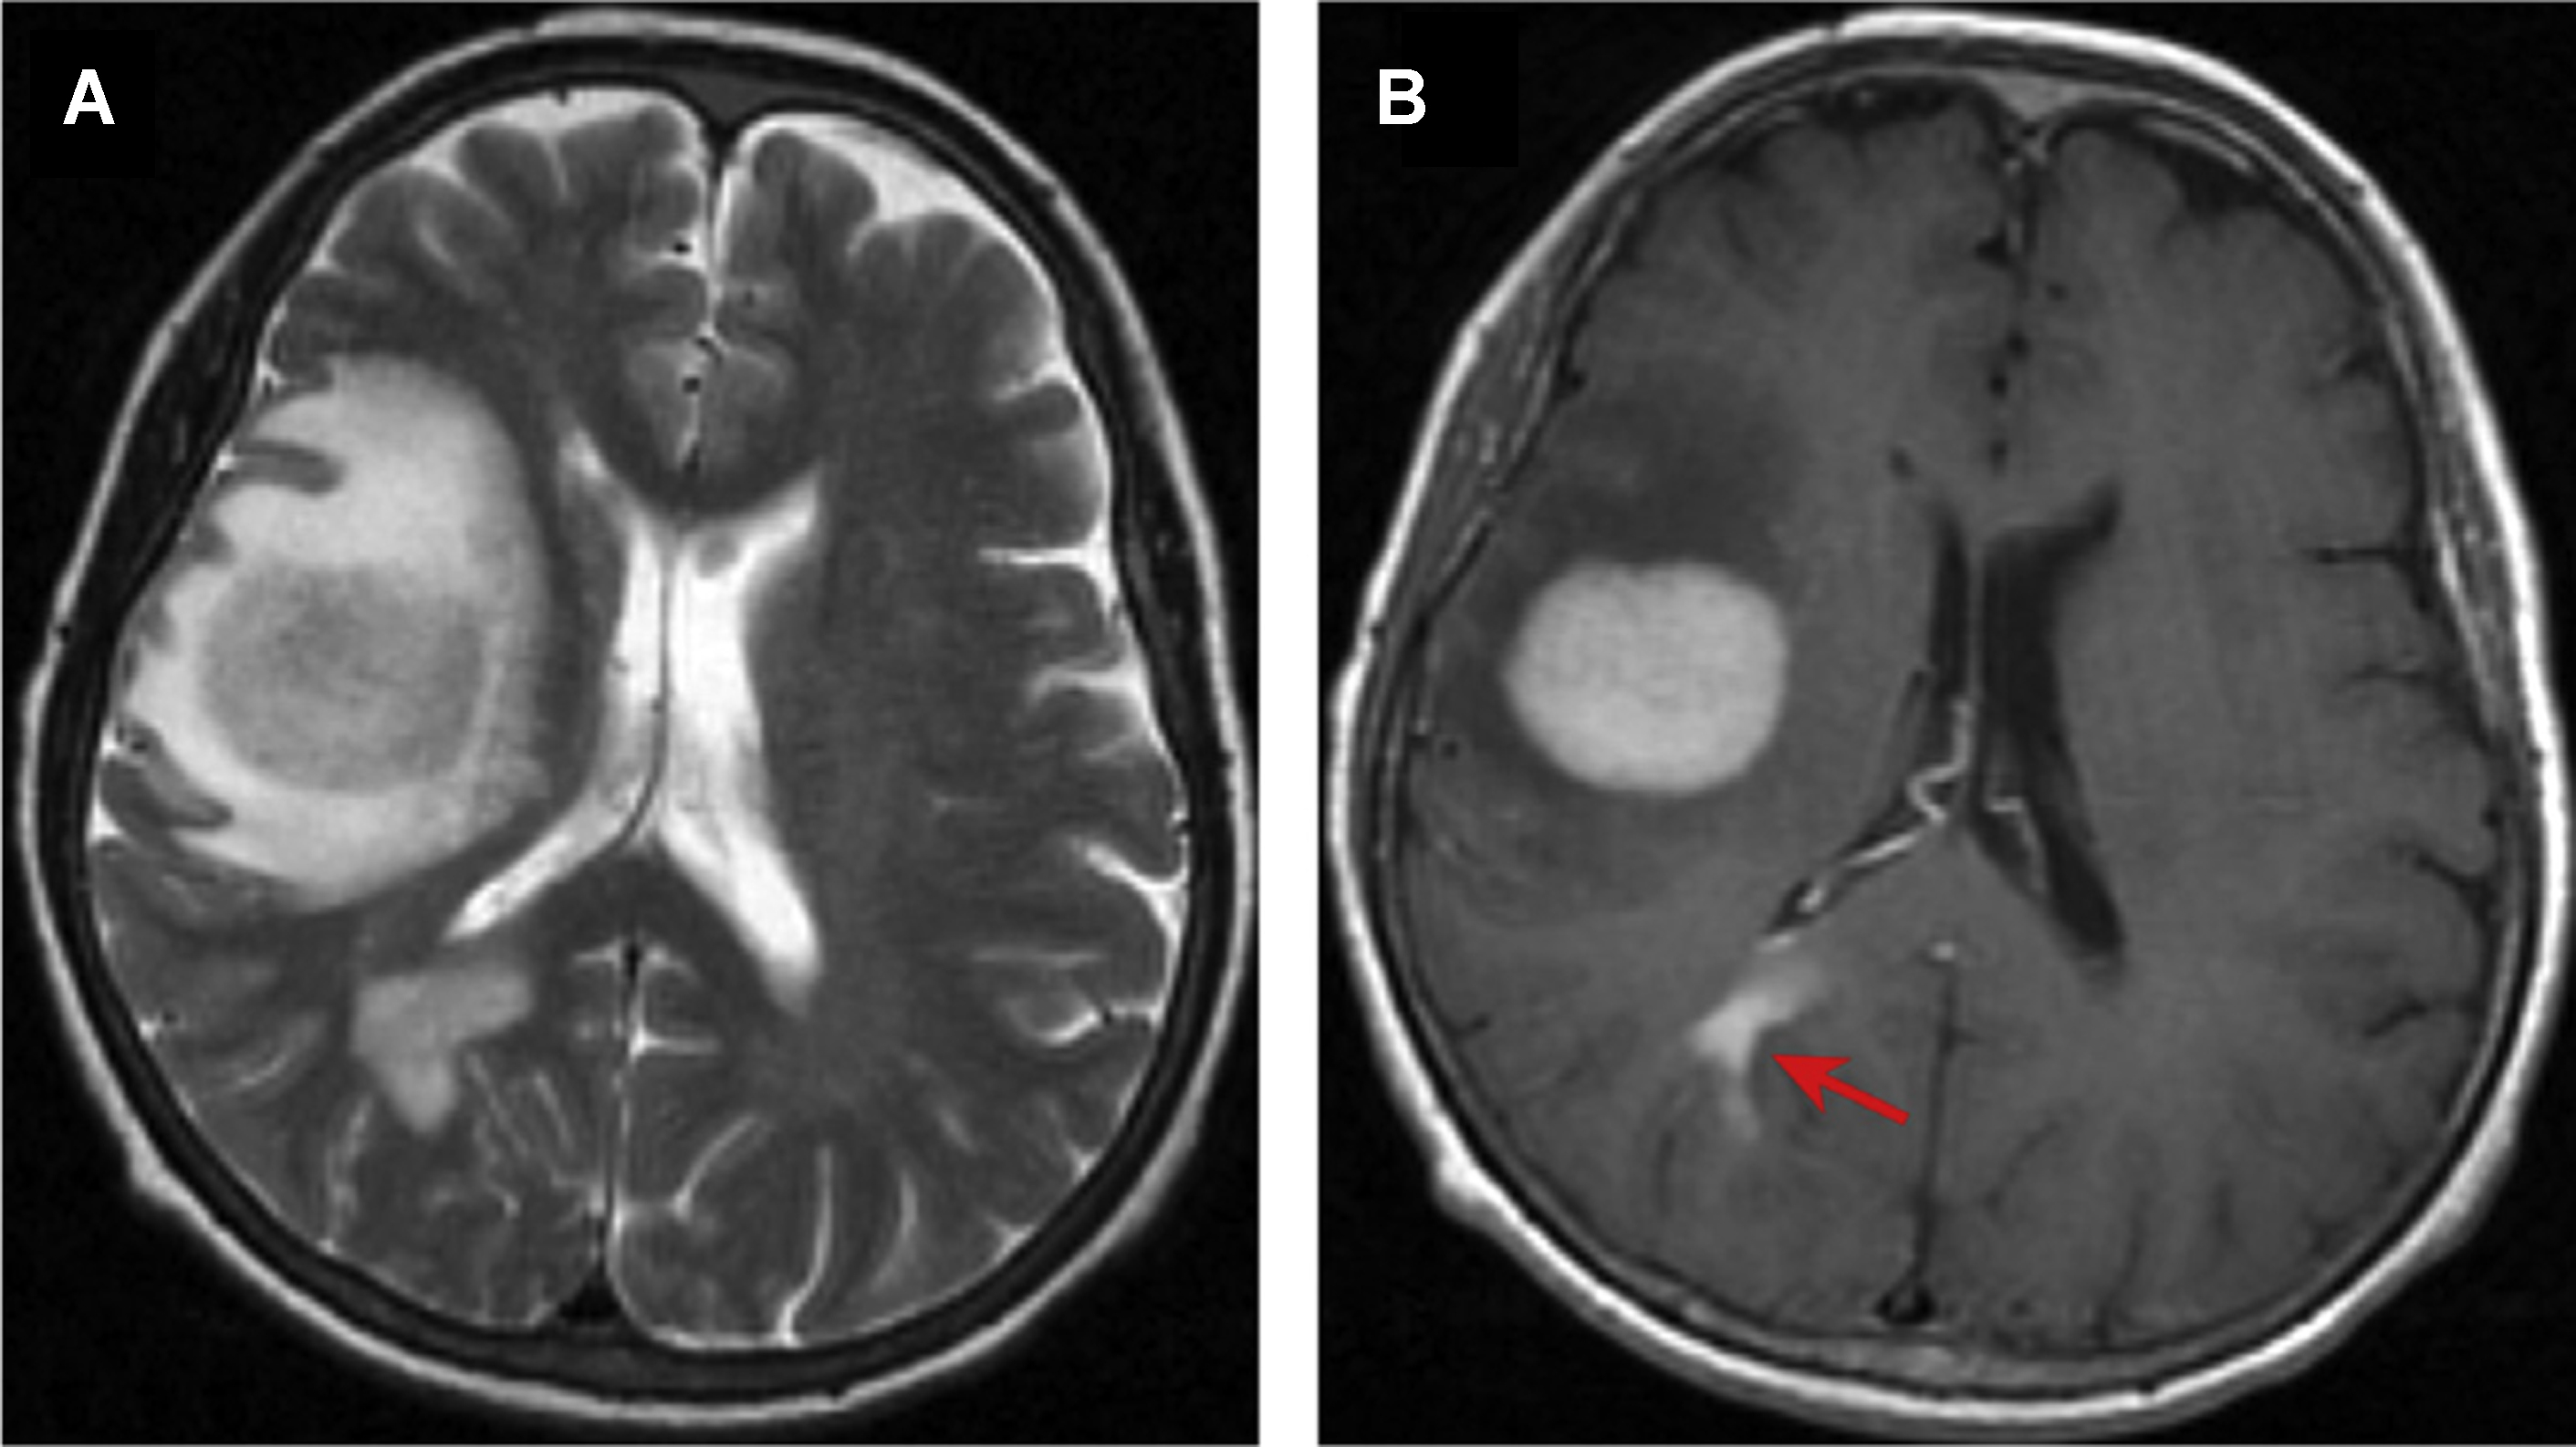

Discover the causes, symptoms, and diagnosis of Corpus Callosum Agenesis (CCA). This comprehensive guide explores how this congenital brain condition affects neural connectivity, neurodevelopment, and cognitive function. Learn about available support resources, clinical management strategies, and what families need to know about navigating life with this rare disorder of brain development.